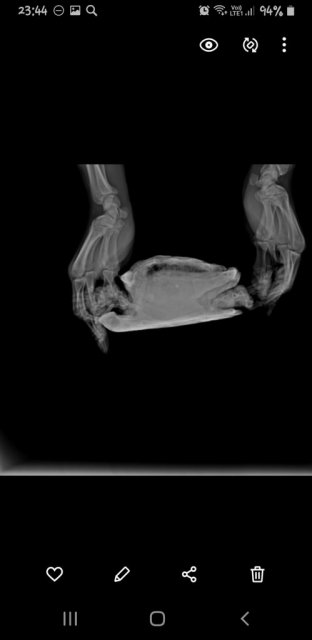

Александр Вдовин Ваше имя: Александр Локация: РФ, Самара Опубликовано: 24 августа 2024 Опубликовано: 24 августа 2024 Не знаю ее возраста, т.к. приползла ко мне на дачу 12 лет назад подростком Недели 3 назад обратил внимание на тяжелое дыхание(возвратно-поступательные движения передних лап с большой амплитудой). Примерно тогда же она стала мало есть и перестала какать. К тому же перестала использовать задние лапы Я живу в Самаре. Эти 3 недели я попадал к людям в ветклиниках, которые считают себя герпетологами. Намучали они моего питомца и отняли время, дарив пустую надежду Сегодня поехал в "Симсон", и черепахе сделали рентген в 3 проекция.Сказали, что всё ужасно. Подскажите сильно опасно ли в данной ситуации консервативное лечение? Возможно ли попасть на операцию к Дмитрию Борисовичу Васильеву без длительного ожидания, если уж без операции никак.Я оставил заявку на прием к нему на сайте " Белый клык" и не знаю увидит ли он её. Мне пока не ответили. К тому же сегодня суббота.Я теряю время. И в Москву я очень быстро добраться не смогу, т.к. мне на самолете нельзя летать.

Консультанты moth Ваше имя: Мария Локация: Москва Опубликовано: 24 августа 2024 Консультанты Опубликовано: 24 августа 2024 @Александр Вдовин здравствуйте! по рентгену тут действительно всё плохо в плане лёгких, их просто нет - они либо пережат содержимым жкт, либо какая-то другая проблема, тут уже должен непосредственно врач-герпетолог хороший смотреть. В Саратове есть хороший герпетолог-хирург, туда Вам проще доехать будет? https://cherepahi.ru/servisy/catalog/rossiya/spravochnik-saratovskaya-obl-saratov/ у них есть стационар, где можно черепаху на лечение оставить

Александр Вдовин Ваше имя: Александр Локация: РФ, Самара Опубликовано: 29 августа 2024 Автор Опубликовано: 29 августа 2024 Какие еще косвенные признаки бывают? Газов у нас на снимке не наблюдается,но легкие как будто чем-то прижаты. Хотя нам Валерия Николаевна пневмонию продиагностировала Поэтому точно узнать прижаты они или поражены точно определить сложно. Пневмония только снизу - тоже странно А чем они бывают прижаты ещё, кроме газов кишечника? Не могу найти информацию нигде Вот снимки. Очень похоже, что они с разными настройками

Консультанты moth Ваше имя: Мария Локация: Москва Опубликовано: 29 августа 2024 Консультанты Опубликовано: 29 августа 2024 @Александр Вдовин тут само качество снимков плохое и мелкое из-за разрешения телефона. Лёгкие могут быть пережаты не только газами, но и скоплением кала в жкт, увеличенным мочевым пузырём. Тут придётся кт ждать.